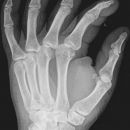

Hand a.p. (dorsovolar)

Beurteilungskriterien

• Kontinuität der drei Karpalbögen (vgl. Handgelenk):

Proximaler Bogen: proximale Gelenkflächenkonturen von Scaphoid, Lunatum und Triquetum

Mittlerer Bogen: distale Gelenkflächenkonturen von Sacphoid, Lunatum und Triquetum

Distaler Bogen: proximale Gelenkflächenkonturen von Capitatum und Hamatum

Fehlende Abgrenzbarkeit, Versatz oder Unterbrechung sind als pathologisch zu bewerten und deuten auf eine Luxation hin.

• M-förmiger Verlauf der Gelenkspalten der Carpometacarpalgelenke? Luxationsstellung in den Carpometacarpalgelenken (meist dorsale Luxation)?

• Gelenkspaltweiten der Carpometacarpalgelenke, der Metacarpophalangealgelenke und Interphalangealgelenke 1 –2mm, der Intercarpalgelenke 1,5 – 2mm

• Täuschungsmöglichkeiten durch Vielzahl akzessorischer Ossikel (abgerundete, zirkulkär-geschlossene Kortikalis), geteilte Handwurzelknochen (Scaphoid, Lunatum, Pisiforme) und Gefäßkanälchen

• Target areas leicht zu übersehender Frakturen:Processus styloideus radii et ulnae, Basen der Metacarpalia (v.a. MCP I) -> großzügige CT-Indikation, Hamulus

Cave: Metacarpale und phalangeale Rotationsfehlstellungen sind konventionell röntgenologisch schwer zu diagnostizieren und zu quantifizieren -> klinischer Befund führend (Fingerstrahl kreuzt bei Beugung im Grundgelenk den benachbarten Strahl), evtl. CT hilfreich.